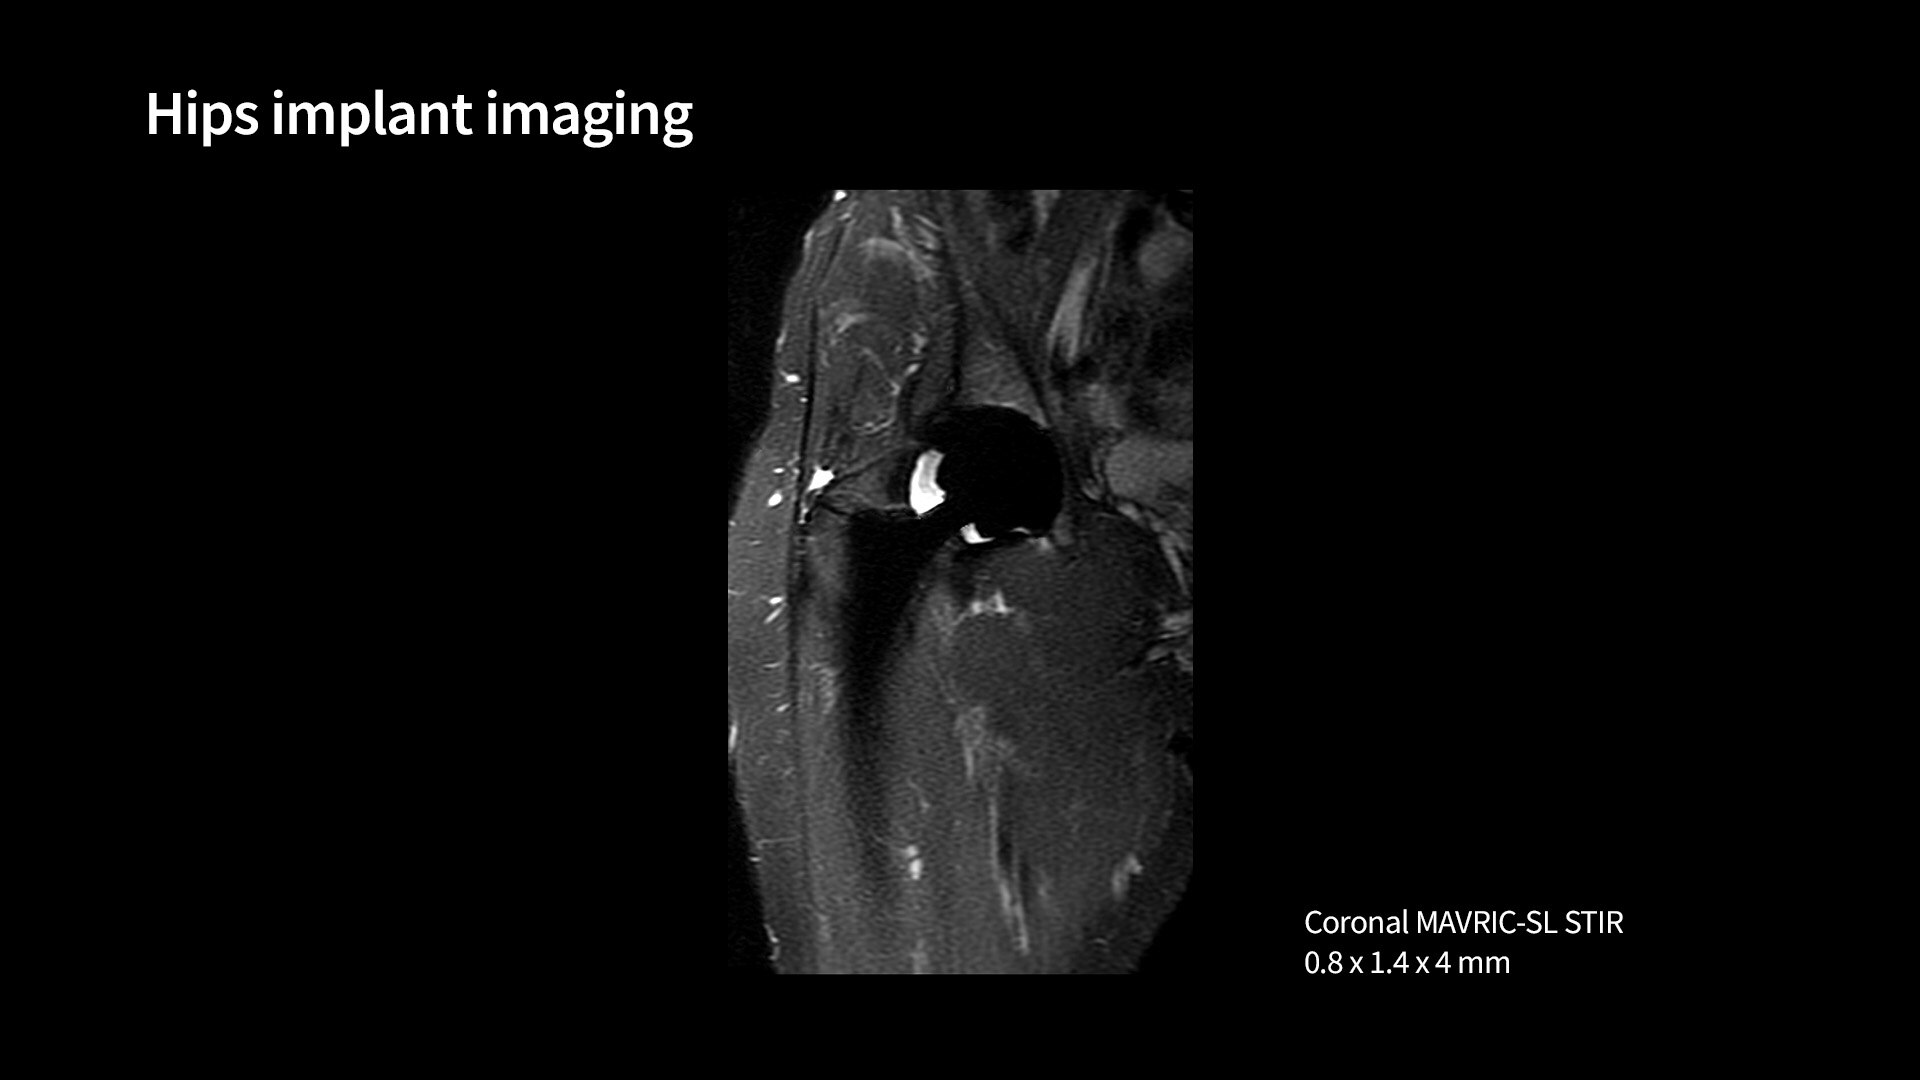

Mavric1040-x-585

Read case study ico-caret-right